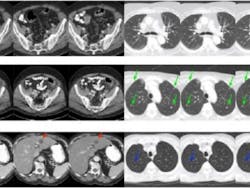

The team addressed this persistent challenge by using a machine learning framework. Specifically, they developed a dedicated deep neural network and compared their best results to the best of what three major commercial CT scanners could produce with iterative reconstruction techniques.

Several radiologists from Massachusetts General Hospital and Harvard Medical School assessed all of the CT images. The deep-learning algorithms developed by the Rensselaer team performed as well as, or better than, those current iterative techniques in an overwhelming majority of cases.